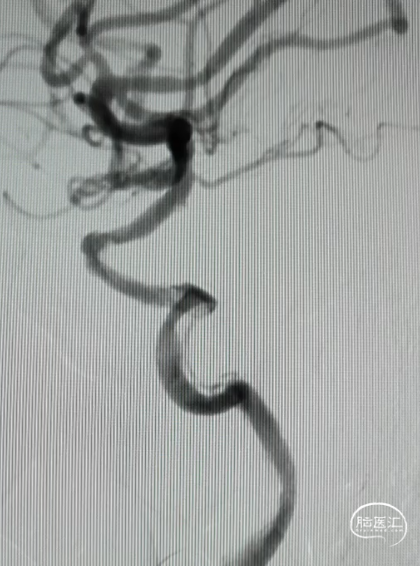

置入4.0*20mm 颅内支架

术后成形良好

术后影像(2024.11.12)

血流监测:连续监测TCD压颈试验证实右侧颈内动脉血流通畅。